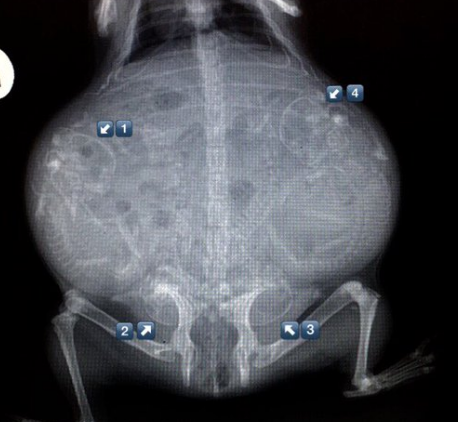

▼怀孕的猫咪